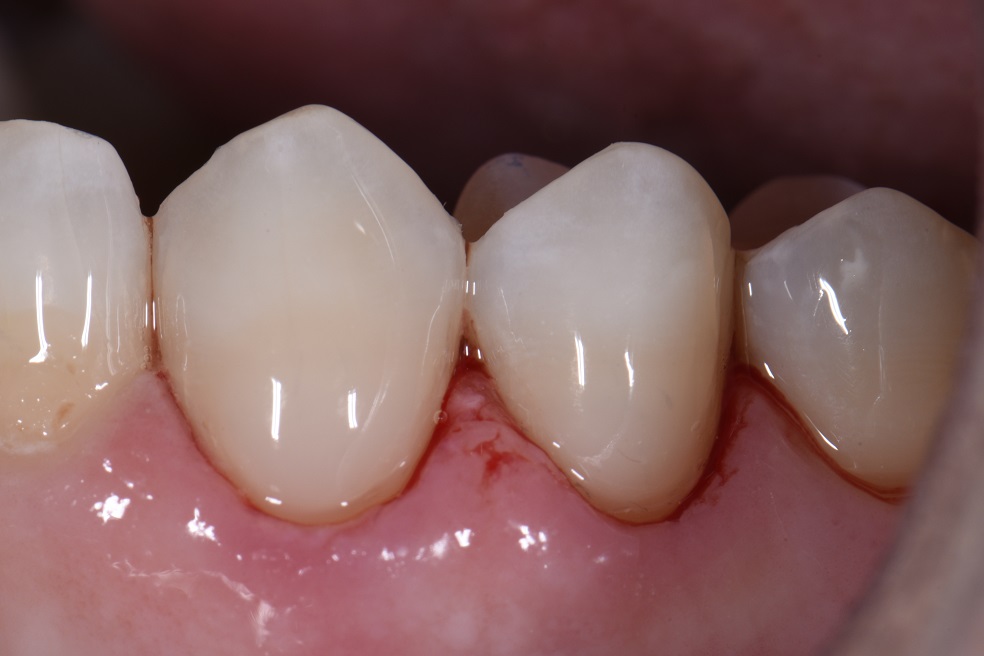

Class V seamless bonded restorations What Is A Class V Restoration In Dental — class iii, iv, and v direct composite restorations are mainly indicated in the restoration of caries lesions (class iii, iv, and v), anterior enamel. Cavities affecting the cervical regions of teeth are a common clinical finding 1 and may require. class v composite restoration failures lie in overconfidence with dentin bonding, a complete lack of standardized preparation. What Is A Class V Restoration In Dental.

Class V Restorations Done Invisibly What Is A Class V Restoration In Dental The class v with subgingival. — class v cavities are multifactorial in origin. Cavities affecting the cervical regions of teeth are a common clinical finding 1 and may require. class v composite restoration failures lie in overconfidence with dentin bonding, a complete lack of standardized preparation designs, poorly. — class iii, iv, and v direct composite restorations. What Is A Class V Restoration In Dental.